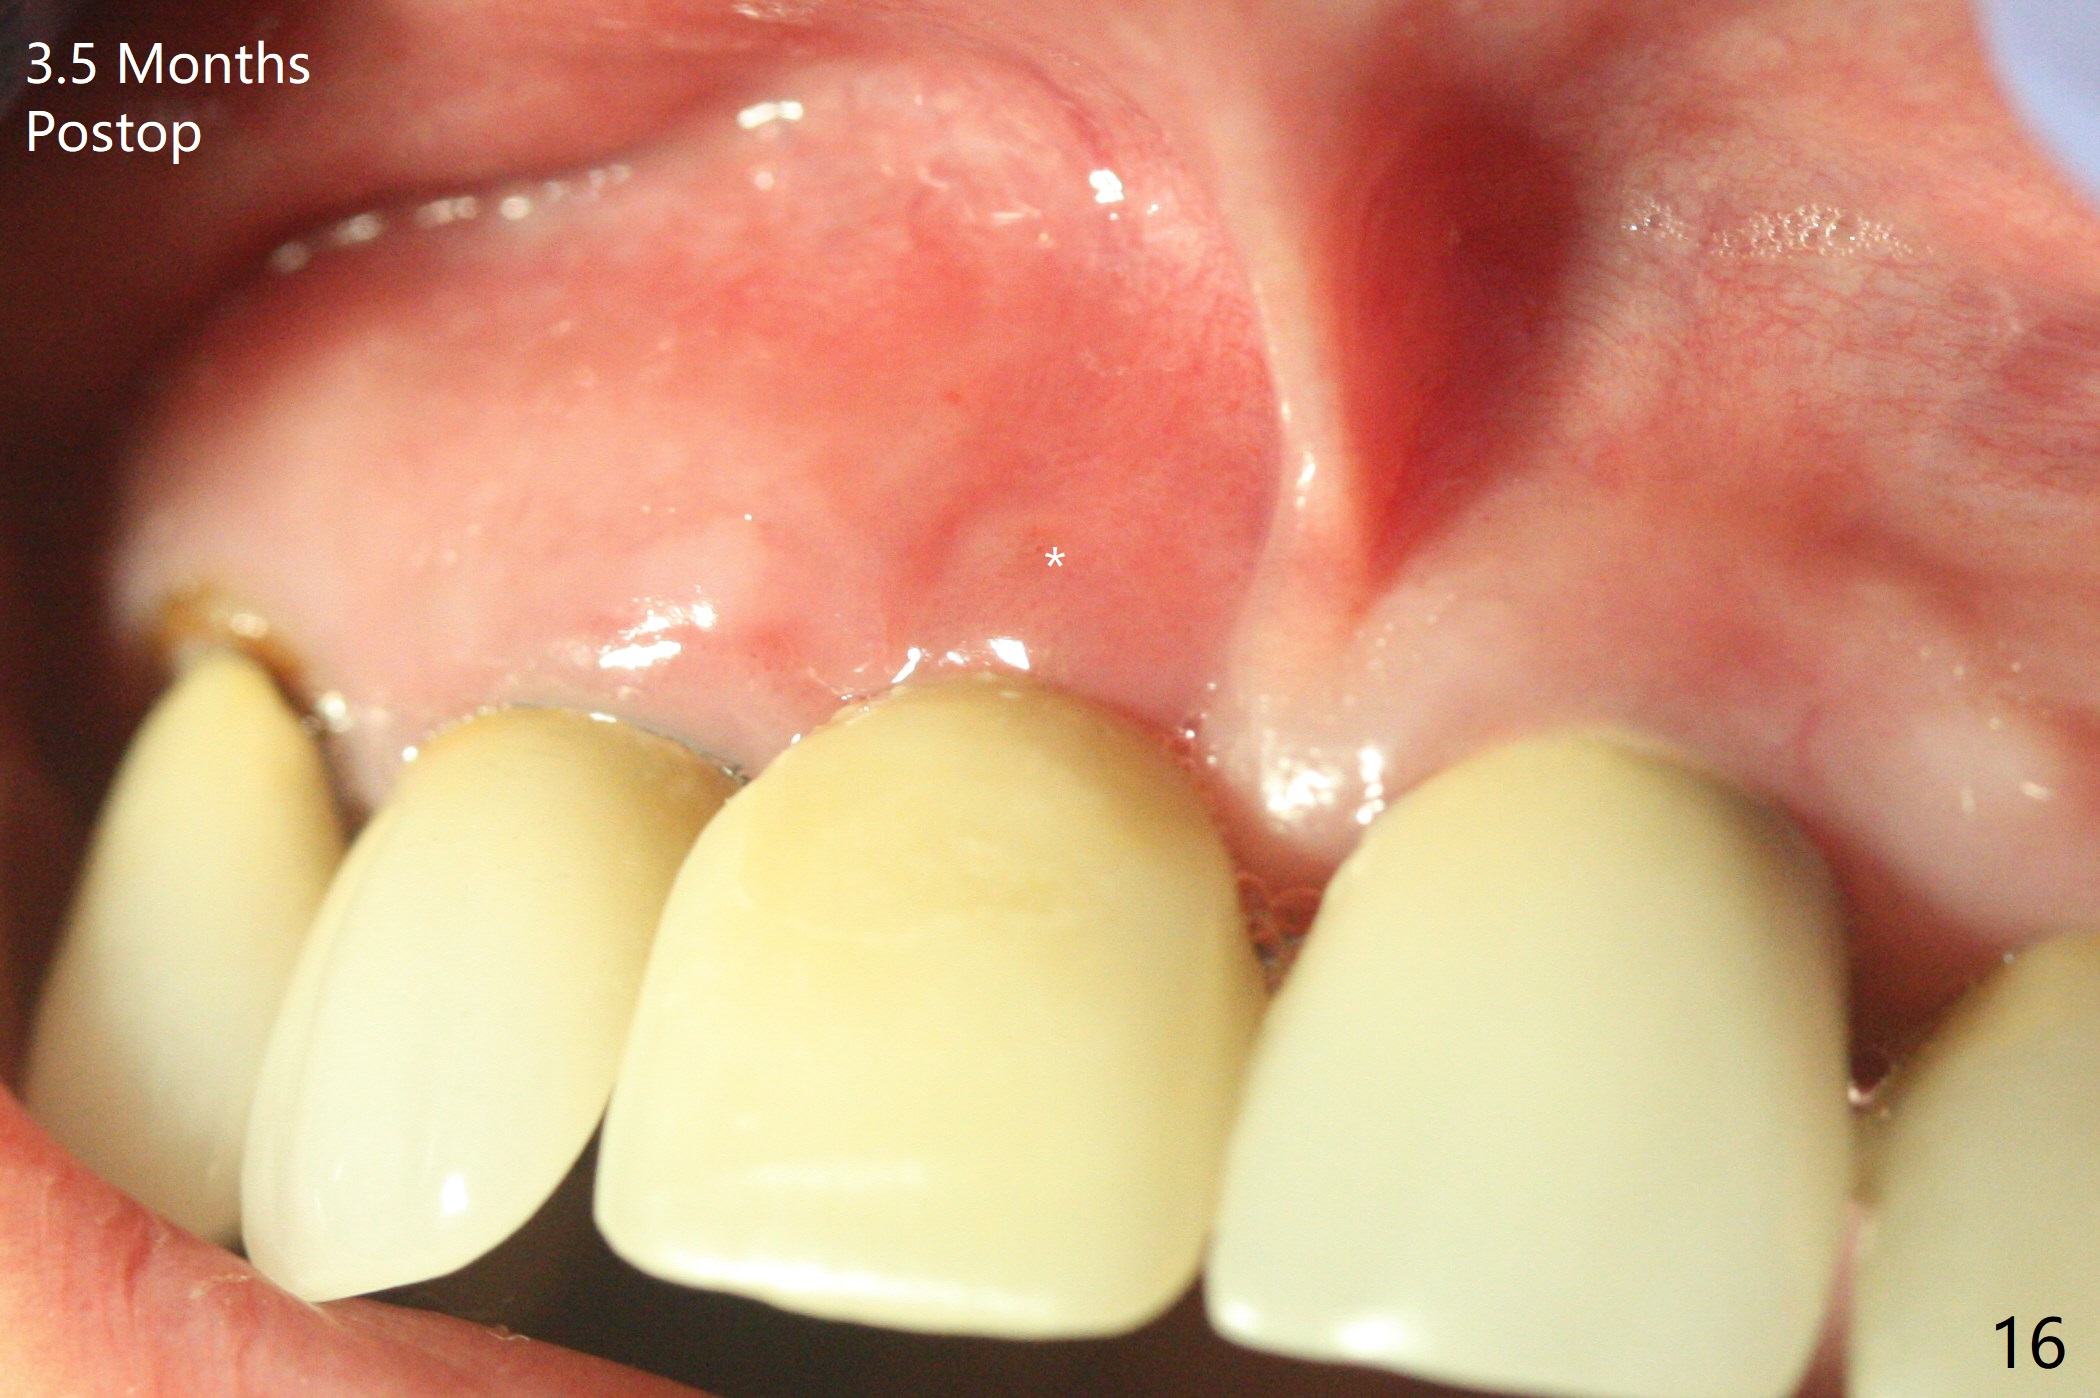

徒手初步钻洞显示方位不对(图一),重新钻洞方位尚可,好像接近鼻底(图二:红线);植入3x11.5毫米一段式植体(图三),3-5个螺纹暴露,植体似乎接近鼻底;旋转植体三趟,植体仿佛卡人鼻底,扭力大约35Ncm,植入粘性骨粉(图四,五:*)前,塞入PRF膜,紧贴颊侧粘膜,促进瘘道愈合。骨粉不仅围绕植体,而且紧贴邻牙牙根(图六(第二轮植骨:overgrafting):<)。病人术后第二周开始使用水牙线,术后三周牙龈健康多了,瘘道消失(图七)。术后六周颊侧骨壁开始塌陷(图八:>),临时牙冠颊侧颈部显得隆起(*)。调整后,牙冠外形改善(图十一至十三),取模前颊侧牙龈缘有可能下降,两个中切牙龈缘可能一致。术后3.5个月骨粉形态(图十四)与术后即刻(图六)有所不同。颊侧牙龈仍红肿轻度触痛(图十五),可能因为临时牙冠不利于局部卫生,所以决定取模制作永久性牙冠。粘固时使用临时胶水,并且涂抗菌素。另外一个可能因素是颊侧骨板薄(图十六:*),细菌感染植体螺纹,永久性牙冠粘固前,拍摄CT(放置cotton roll),必要时,植骨。永久性牙冠远中有缝隙,为了预防病人后悔,使用临时性粘固剂固定(图十七)。Return to No Caries DIO 下一个病例 一段式植体边缘制备 导板与内提升 Xin Wei, DDS, PhD, MS 1st edition 12/22/2020, last revision 06/15/2021